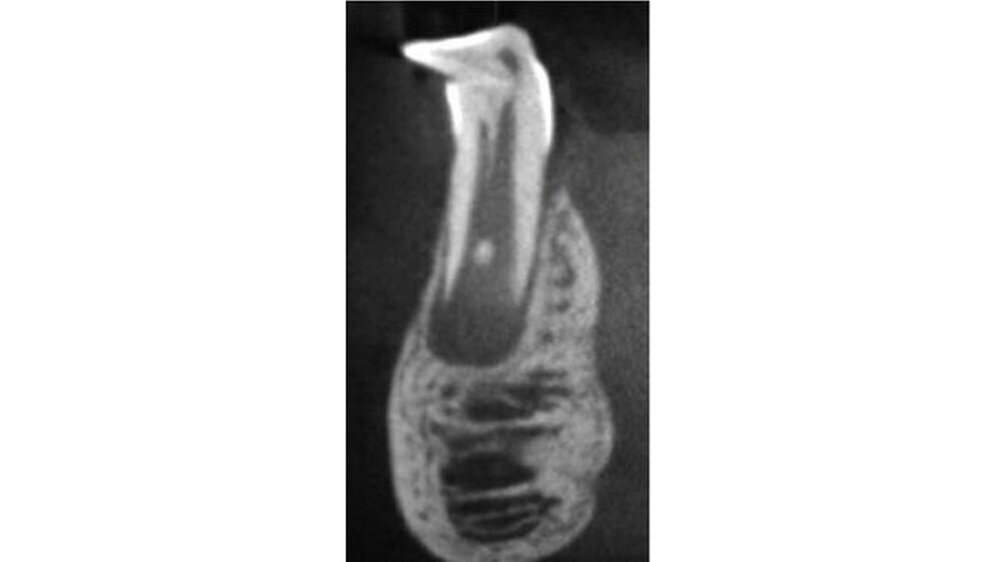

Alles, was bereits vollständig mineralisiert ist, ist nicht oder kaum betroffen. Bei einer axialen Stauchung des bleibenden Zahnkeims durch die Milchzahnwurzel kommt es zur sogenannten kalizotraumatischen Linie, bei einer erheblichen nicht-axialen Stauchung zur Verlagerung der bereits mineralisierten Zahnhartsubstanz. Die nach dem Unfall weiter fortschreitende Mineralisation des Zahns folgt nicht etwa der neuen Lage des Zahns sondern wählt den Weg, der ihr genetisch vorgegeben wurde - unabhängig von der Lage und Position des bereits mineralisierten Anteils.

Die Folge ist ein mehr oder weniger ausgeprägter scharfer Knick im Zahn. Davon abzugrenzen ist die ebenfalls unfallbedingte vestibuläre Wurzelkrümmung (Vestibular root angulation), die eine Biegung der Zahns/der Wurzel und keinen Knick aufweist. Diese entsteht häufiger nach Milchzahnavulsion, wo der Zahnkeim langsam eine andere Durchbruchsrichtung einschlägt. Ursache ist unter anderem eine lokale Fibrosierung im Bereich der Milchzahnalveole.

Dilazeration (Abb. 1 bis 7) kann zur Durchbruchsstörung des betroffen Zahns führen. Fast immer sind auch Farb- und Formanomalien des Schmelzes zu beobachten. Die Erhaltungsmöglichkeit solcher Zähne hängt primär von der Schwere und Lokalisation der Missbildung, aber auch vom Grad der Farb- und Strukturanomalie ab. Malformationen im mittleren oder apikalen Wurzeldrittel sind ohne Einfluss auf den dentogingivalen Verschluss und haben in der Regel wenig Einfluss auf den Zahnerhalt - die Pulpa bleibt hier in den meisten Fällen vital.